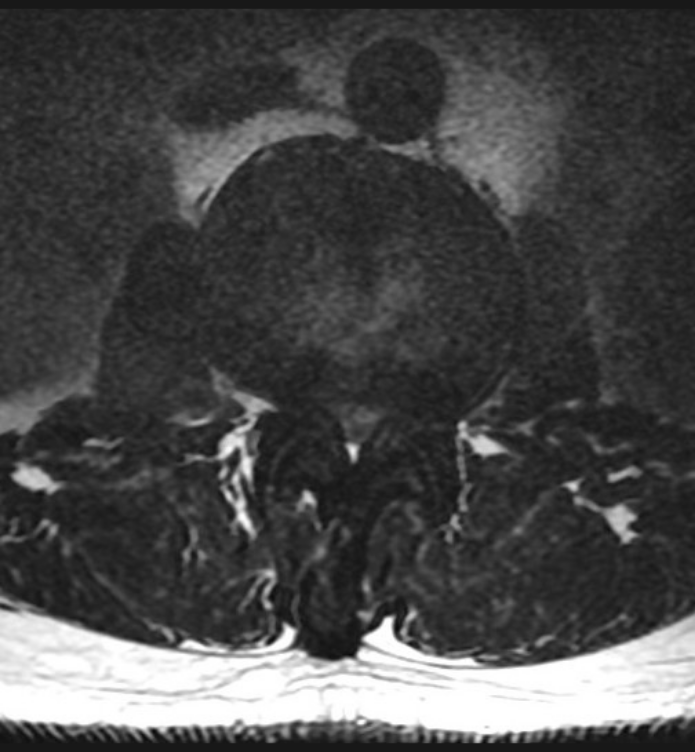

Basit Omurga ve Omurilik Anatomisi Omurga, 33 adet omur kemiğinden oluşur. Bu kemiklerin 7 tanesi boyun omuru, 12 tanesi sırt omuru, 5 tanesi bel omurudur. Beş tanesi birleşmiş olarak sakrum denilen kemiği ve 4 tanesi yine birleşmiş olarak koksiks denilen kuyruk sokumu kemiğini oluşturur. Omurganın görevi omuriliği korumak ve gövdeyi dik pozisyonda tutmak için destek […]